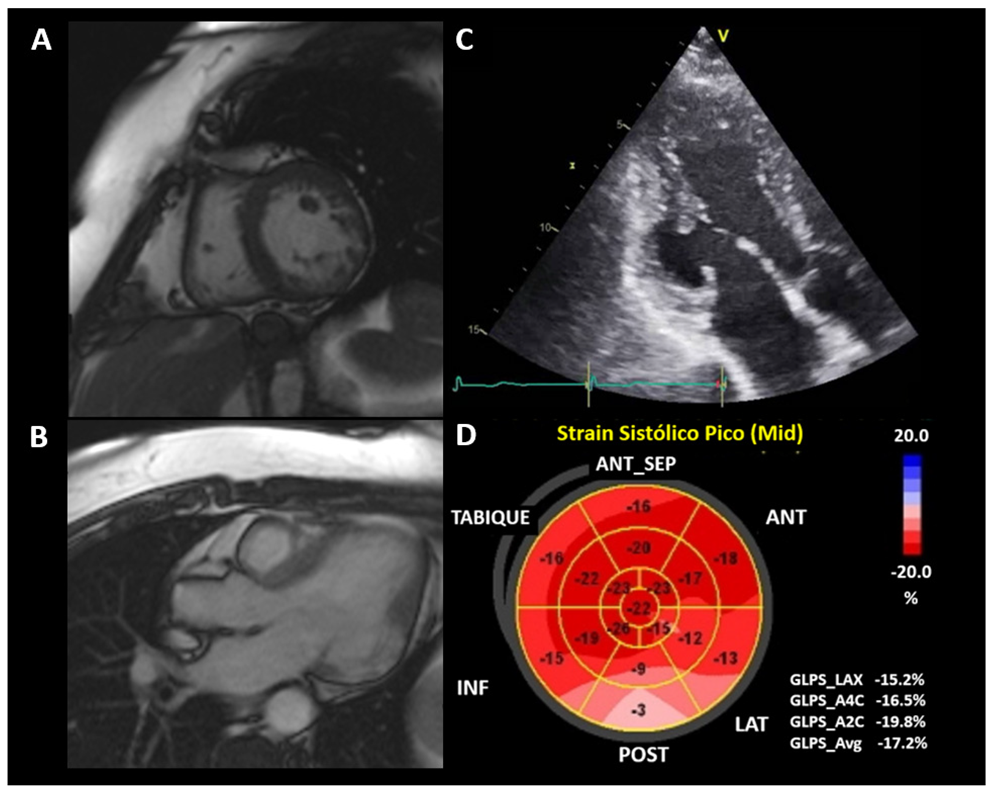

The study of segmental mobility alterations is subjective, so the evaluation of deformation by two–dimensional speckle tracking (2DST) can become a useful tool in the early stages by identifying alterations in areas without apparent involvement [5,123]. The use of 2DST is less useful in patients with obvious segmental mobility disorders (Figure 6), but it still serves as a tool to assess the heterogeneity of systolic contraction (mechanical dispersion); these alterations are associated with ventricular arrhythmias independent of LVEF [122,124].

LV apical aneurysms are a pathognomonic finding [98,122] of CCC that may be useful for differential diagnosis with dilated cardiomyopathy (Figure 7). Another frequent presentation site is the inferolateral wall of the LV, although they are not exclusive to these sites [14]. The presence of aneurysms frequently accompanies disease progression to LV systolic dysfunction, where three-dimensional echocardiography and the use of contrast agents offer advantages for their evaluation [122,124]. In advanced stages of the disease, these are characterized by generalized hypokinesia and LV systolic dysfunction, the latter being a predictor of mortality in CCC [124].

The onset of LV diastolic dysfunction can occur early in the disease, even in asymptomatic forms of the chronic stage, with a prevalence of up to 10% [114]. Diastolic and systolic dysfunction coexist in all patients in the advanced stages of the disease. Right ventricular (RV) systolic dysfunction is a marker of poor prognosis.

6.4. Cardiac Magnetic Resonance (CMR) Imaging

CMR makes it possible to identify myocardial fibrosis using late gadolinium uptake as a contrast agent [125]. Up to 20% of asymptomatic chronic-stage patients without LV segmental motion abnormalities have signs of fibrosis due to CMR.

The extent of myocardial fibrosis correlates with the severity of LV systolic dysfunction and the occurrence of ventricular arrhythmias [124]. Late gadolinium enhancement (LGE) can be transmural (44%), intramyocardial (32%), subendocardial (11%), epicardial (11%), or subepicardial [70]. The most frequently affected areas are the inferolateral wall and the apex (Figure 8). Transmural enhancement of two or more segments is a strong predictor of ventricular arrhythmias independent of other factors such as LVEF, age, gender, and extent of fibrosis. The extent of myocardial fibrosis has the potential to become an indication for implantable cardioverter defibrillator (ICD) in patients with CCC [122].